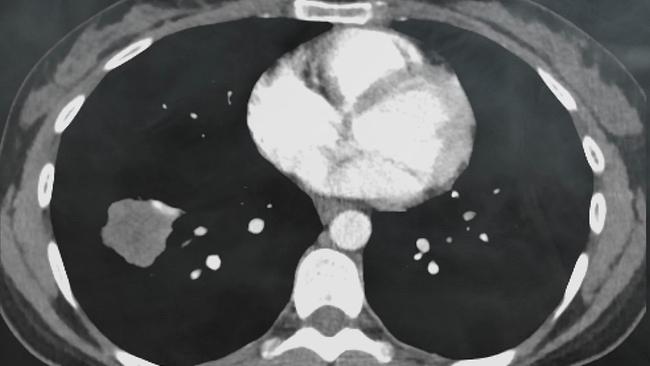

Was das Rauchen angeht, hat Österreich einen unrühmlichen Platz im europäischen Spitzenfeld. Rund 24 Prozent der Erwachsenen rauchen täglich. Das gilt bisher als Hauptursache für die Entstehung von Lungenkrebs. Rund 5000 Frauen und Männer erhalten jährlich diese Diagnose. Das Alarmierende: Immer öfter bekommen auch Nichtraucher ein Lungenkarzinom.

Am 19. November ist Welt-COPD-Tag – ein Anlass, um auf die chronisch obstruktive Lungenkrankheit, von der 400.000 Menschen in Österreich betroffen sind, aufmerksam zu machen. COPD ist eine weitere Erkrankung, die vor allem durch Rauchen, aber auch durch Luftverschmutzung verursacht wird. Auch Nichtraucher*innen sind zunehmend gefährdet. Die fortschreitende Atemwegserkrankung verläuft in verschiedenen Stadien und ist nicht heilbar. Die Symptome von COPD treten oft schleichend auf - zu diesen zählen chronischer Husten, später auch Auswurf und Atemnot. Wird die Erkrankung nicht frühzeitig erkannt, kann sie die Lebensqualität der Betroffenen erheblich beeinträchtigen, alltägliche Aktivitäten wie Treppensteigen oder längeres Gehen nahezu unmöglich machen, und schließlich zum Tod führen. Eine frühzeitige Diagnose und eine gezielte Behandlung sind entscheidend, um das Fortschreiten der Krankheit zu verlangsamen, erklärt Dr. Michael Studnicka, Leiter der Universitätsklinik für Pneumologie & Lungenheilkunde am Landeskrankenhaus Salzburg.